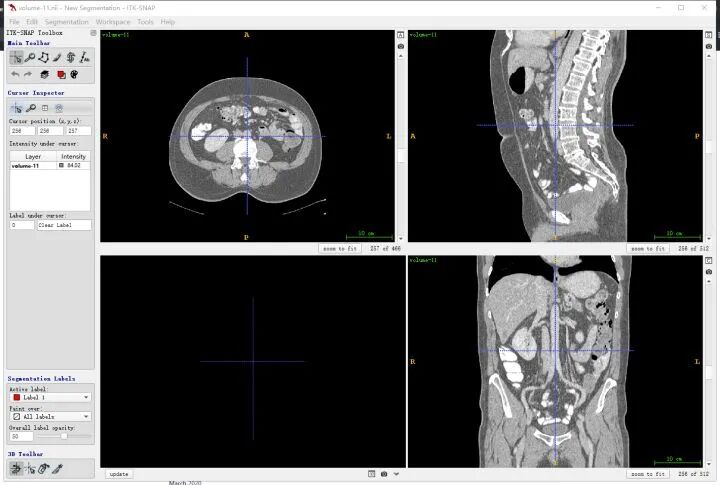

首先要明确一下和人体对应的方向,其中三个窗口对应三个切面,对应关系如下图所示,按照字母索引即可。例如,左上图对应R-A-L-P这个面,是从脚底往头部方向看的切面(即z方向),另外两张类似。

同一个slice在ITK-SNAP可视化结果(注意这里(x,y,z=(256,256,101)),因为itk-snap默认从1开始索引):